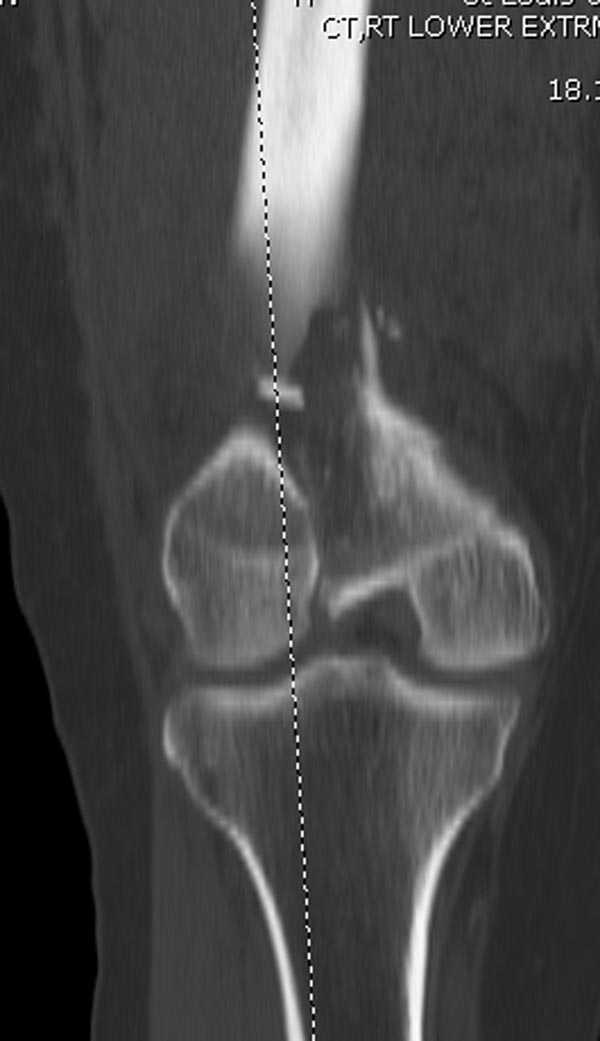

[Ortho] Дистальный перелом бедра

Бесспорно, предлагаемый ретроградный метод имеет свои преимущества, но имеется опасность при манипуляции интрамедуллярным гвоздем расколоть мыщелки.

Раскол можно предупредить шурупами, но короткий дистальный фрагмент навряд ли позволит добиться адекватной стабильности конструкции. Стандартные гвозди не рассчитаны для таких переломов, и если все таки желаете провести фиксацию гвоздем, тогда надо заказывать специальный custom made nail т.е. с расширенной возможностью дистальной блокировки.

Поэтому такие меж и над- мыщелковые переломы более предпочтительным считается фиксировать мыщелковыми пластинами

Устанавливается из малого разреза "не вскрывая сустав" со стороны латерального мыщелка, и Insertion Jig позволяет установить пластину "мостовидно" перкутанно в проксимальном отделе, "не вскрывая и не трогая" место перелома.